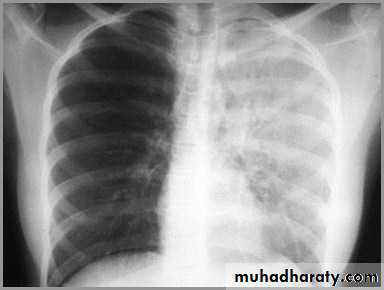

Differentiating the Causes of an Opacified Hemithorax

Pneumonia of an entire lung

pneumonia

The hemithorax is opaque and there isno shift of the heart or tracheaThere may be an air bronchogram sign present